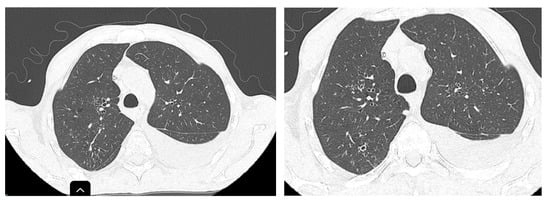

Two months after the initiation of treatment (Figure 3), regression of interstitial densities, “tree-in-bud” micronodules, and the regression of ascites were noted. Although the lesions probably associated with tuberculosis were ameliorated, new pulmonary nodular lesions were detected, as well as an increase in a pre-existing nodule (Figure 4), most likely in the context of the underlying neoplastic pathology, whose treatment was interrupted during tuberculosis treatment.

Figure 3. Improvement in “tree-in-bud” infiltration in the posterior segment of the right upper lobe (RUL) after 2 months of treatment.

Figure 4. Enlargement of the pre-existing nodule and appearance of a new nodular formation at the superior lingular level.